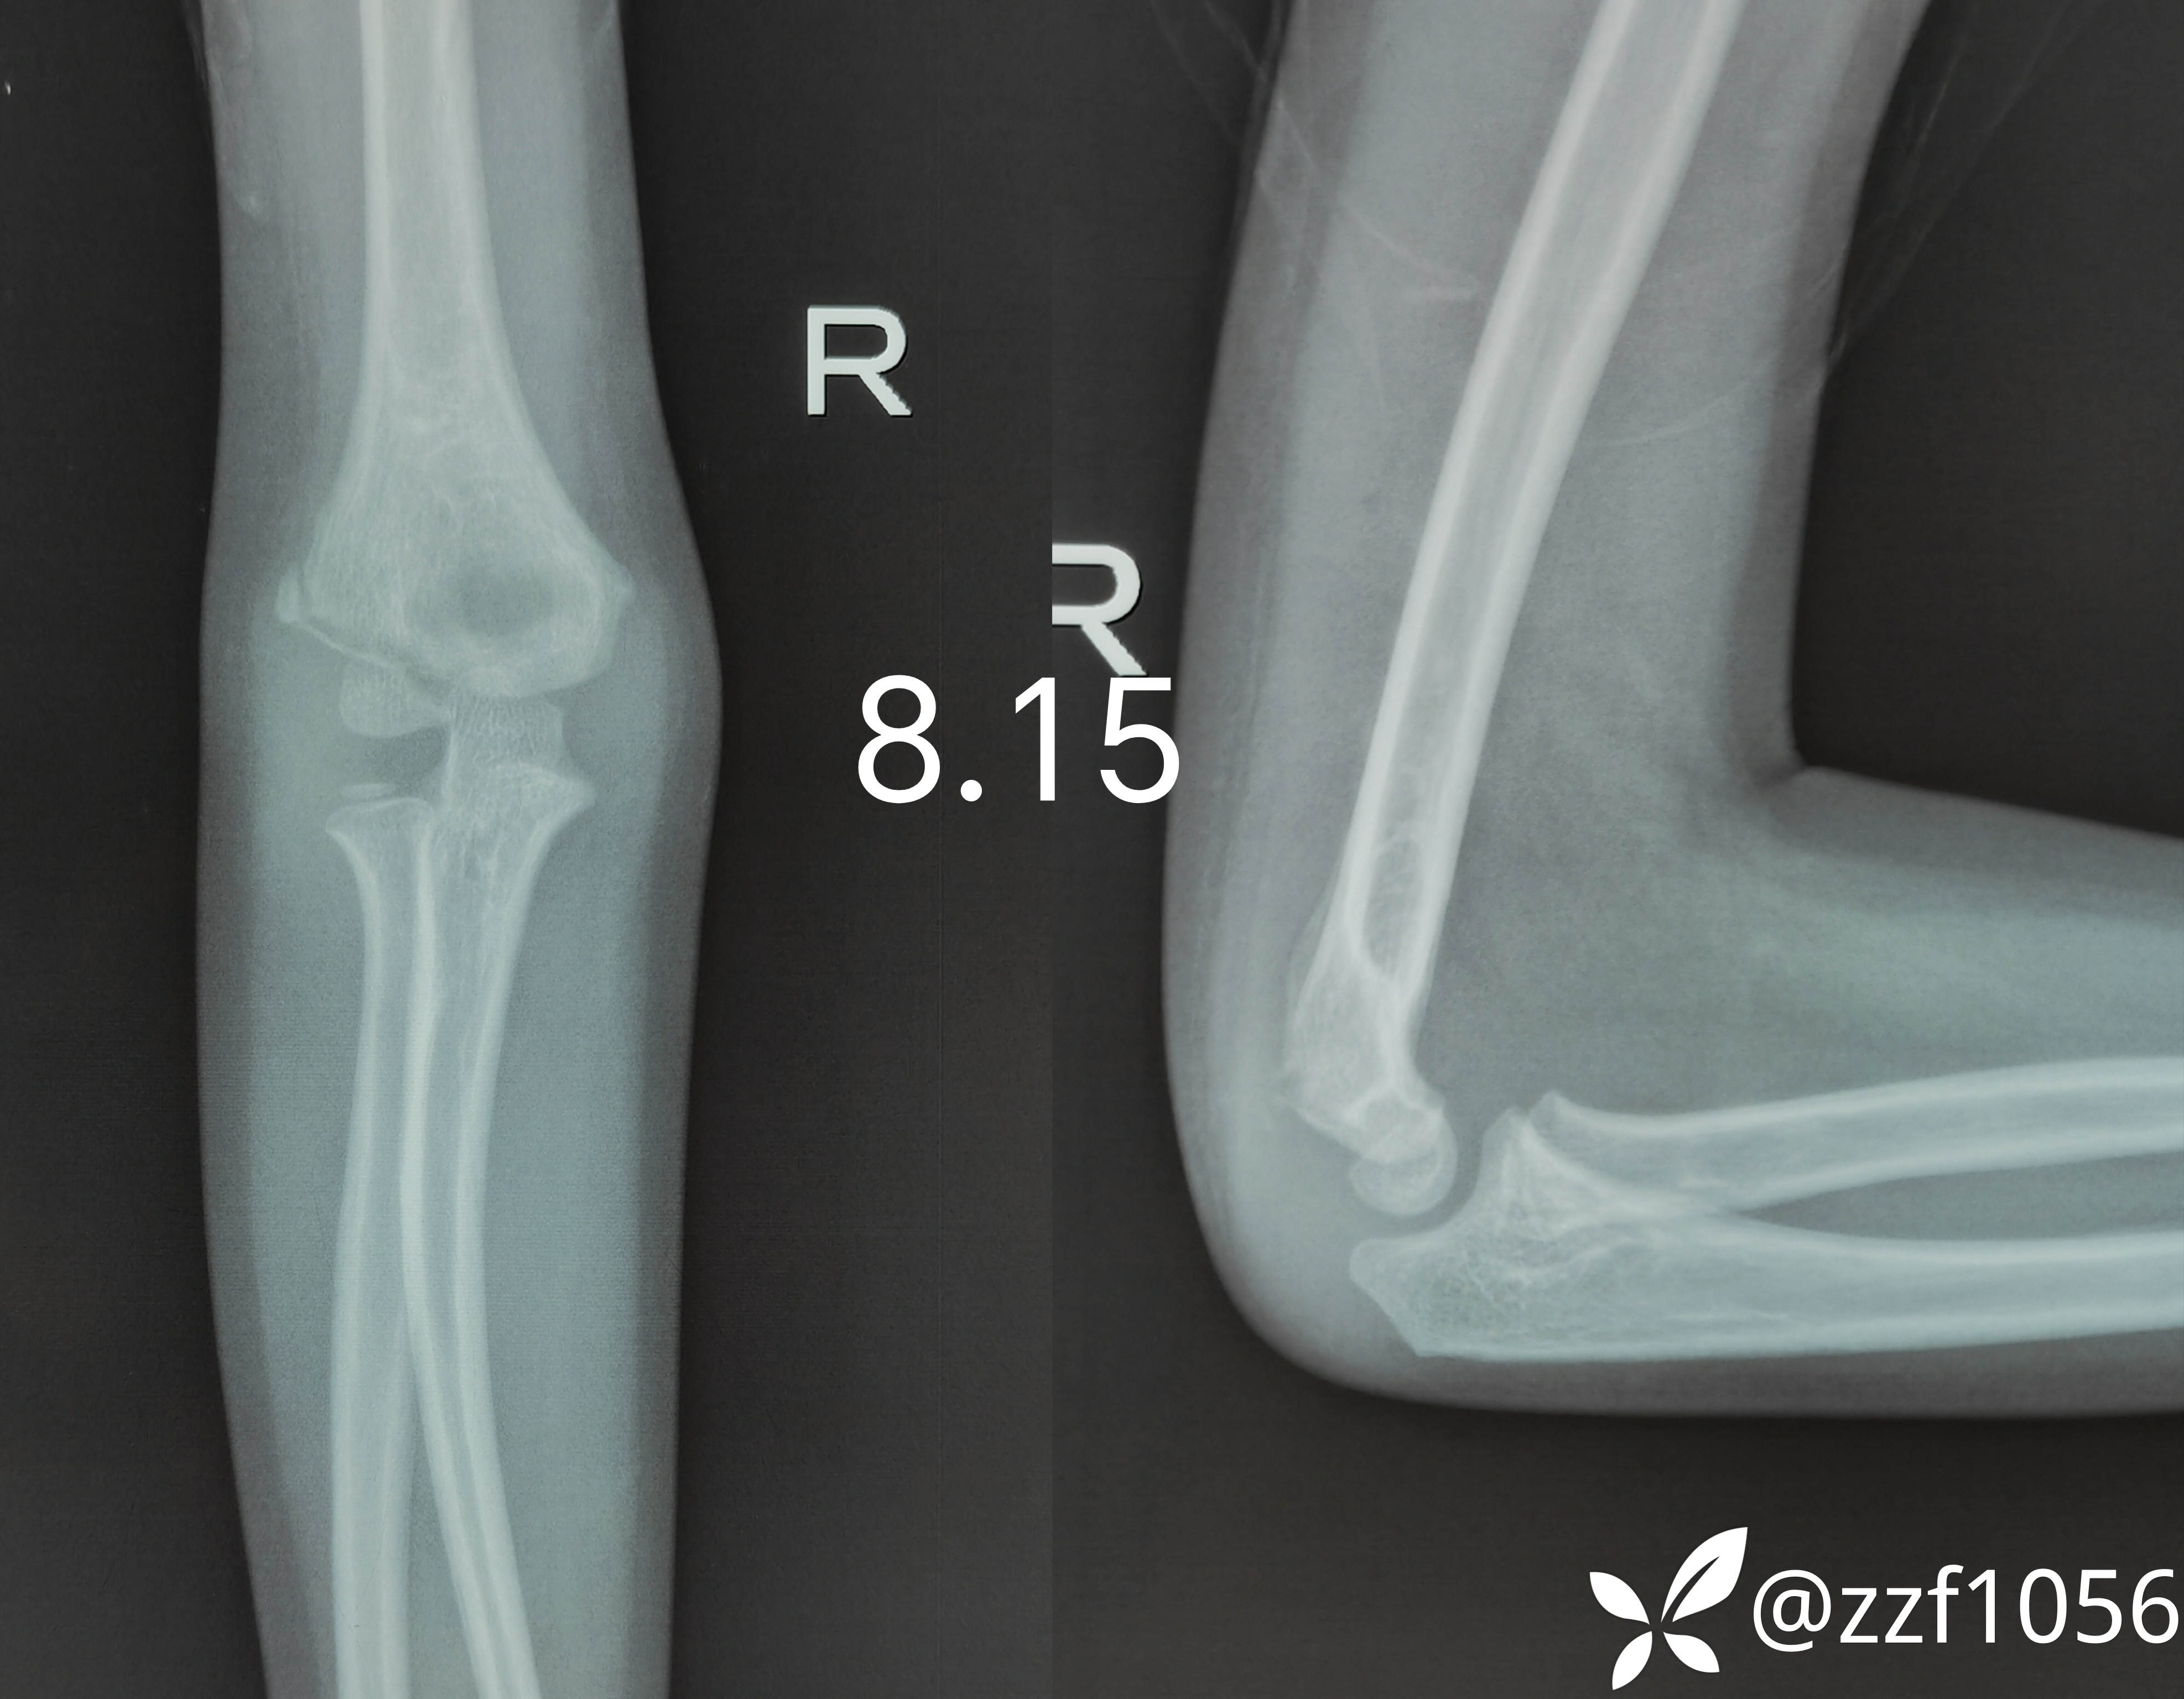

保守半月昨日再次来我院就诊,门诊摄片显示

正好被我遇见瞄了一眼片子,感觉比较异常

建议做个ct

现在距离外伤已整一月,目前右肘外侧压痛,伸屈功能欠佳